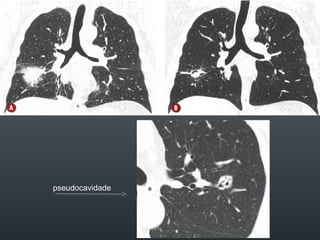

O documento discute vários conceitos radiológicos incluindo consolidação, atelectasia, nódulos, pseudocavidades e padrões intersticiais, fornecendo definições, sinais e diagnósticos diferenciais para cada tópico. Ele também discute a redução da atenuação pulmonar e fornece um link para mais informações.